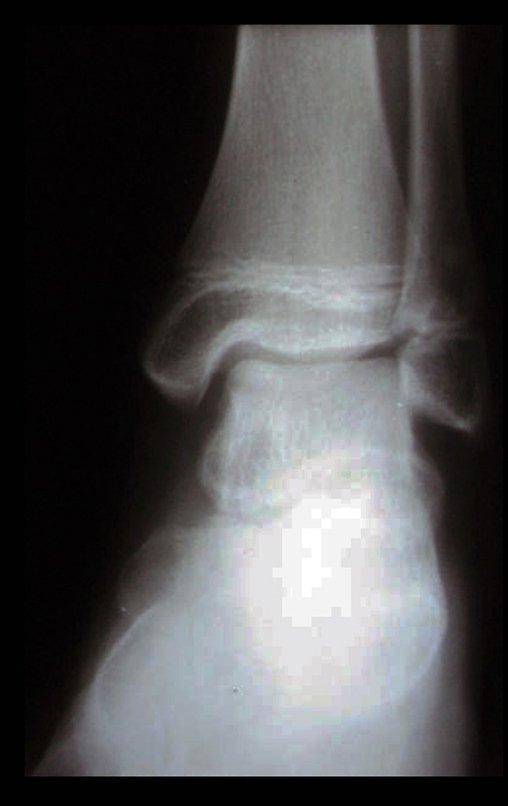

Cuatro meses después de la radioablación, debido a la persistencia del cuadro doloroso, se realizó nueva tomografía el 17/08/2014.

Las imágenes de esta tomografía computarizada, tras la radioablación, se analizan en las figuras 15 a 20.

¿Cuál es el significado de esta imagen? ¿Cicatriz? ¿Persistencia de la lesión? ¿El paciente sigue teniendo los mismos síntomas?